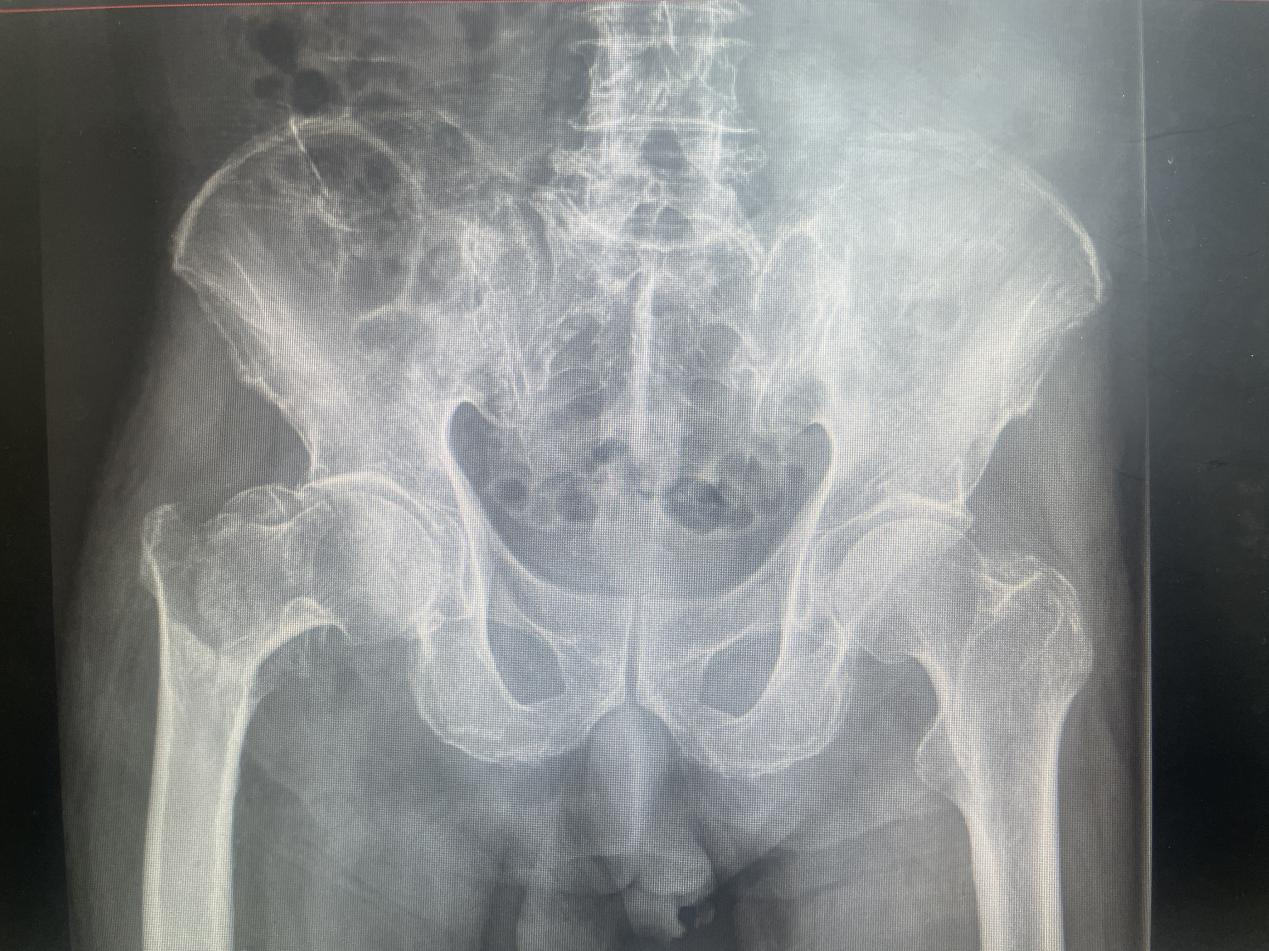

多学科联合诊疗让高龄老人放“髋”心 近日,优米app下载ios骨科关节中心主任惠正广团队启动多学科联合()诊疗,组织呼吸科、介入科、心血管内科、神经内科、手...